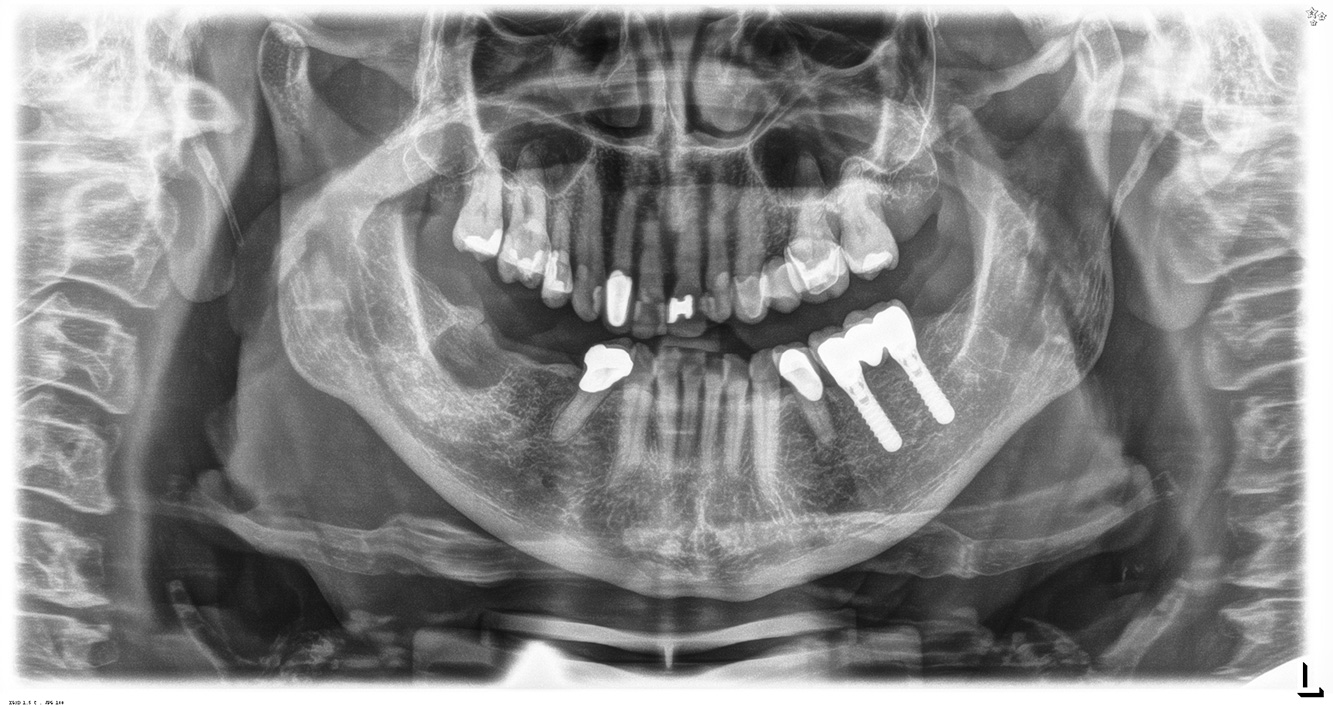

La paciente de 68 años no tiene enfermedades previas relevantes de la salud general ni toma medicación; sus hábitos alimentarios tampoco suponen un riesgo especial. La paciente tiene dos implantes (tercer cuadrante, desde hace cinco años) y una enfermedad previa periodontal (periodontitis en etapa IV, grado B) con pérdida dental. Actualmente las condiciones periodontales son estables, pero la periodontitis aumenta de manera determinante las complicaciones biológicas cuando se realizan implantes y puede ocasionar la pérdida de un implante (21). Para la sesión de profilaxis se hacen cuatro recomendaciones.

Dado que la paciente no tiene factores de riesgo especiales con efectos específicos para los dientes, las necesidades determinadas a partir de la salud oral son determinantes. Se recomienda un estado periodontal detallado una vez al año. De esta forma, es posible responder a la posible progresión de la enfermedad periodontal previa o al desarrollo de periimplantitis a tiempo.

Debido a la situación del implante con la enfermedad periodontal previa, la paciente tiene riesgo de desarrollar periimplantitis; se recomienda un intervalo de recuperación de tres a cuatro meses.